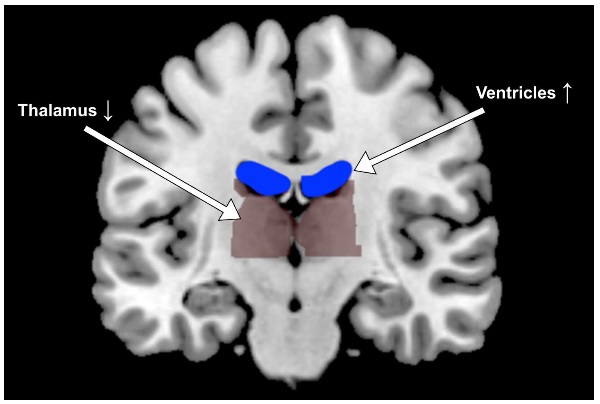

D’autres études ont déjà alerté sur les effets de la déshydratation sur le cerveau : cette équipe de l’Institut de technologie de Géorgie revient sur les effets de la déshydratation sur la forme et l'activité du cerveau humain et décrypte comment ces modifications impactent les performances cognitives. Des travaux présentés dans les Physiological Reports qui révèlent jusqu’à des ventricules expansés et un thalamus diminué.

Ici, par scanners cérébraux lors de l’accomplissement d'une tâche simple et répétitive, les chercheurs montrent, chez des bénévoles ayant accepté de peu s’hydrater et de beaucoup transpirer (visuel ci-dessous) que :

- certaines zones du cerveau présentent des changements évidents : lorsque les participants pratiquent l’exercice, transpirent puis boivent de l'eau, les espaces remplis de liquide appelés ventricules au centre de leur cerveau se contractent. Mais avec l'effort et la déshydratation, les ventricules « font » le contraire et s’élargissent ;

Chaleur, effort, déshydratation : ces changements structurels s’avèrent remarquablement cohérents entre les individus, cependant les différences de performance dans les tâches ne peuvent pas être expliquées par ces seuls changements de taille de ces zones cérébrales. Des changements dans les schémas de tirs de neurones sont également constatés en cas de déshydratation…